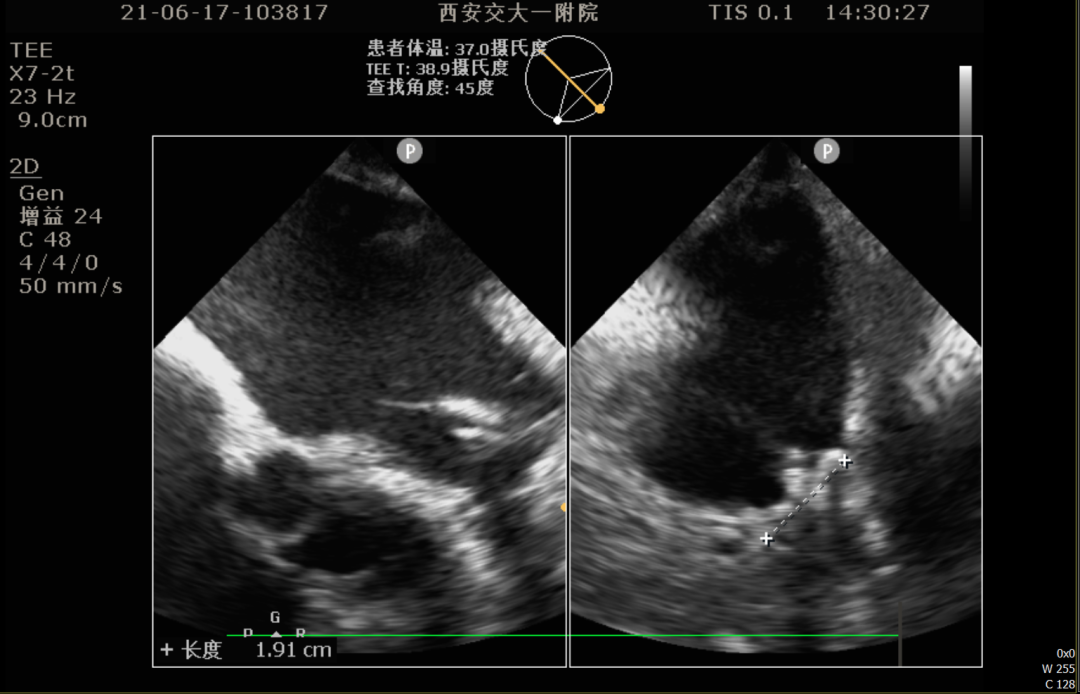

TEE测量左心耳数据:

TEE测量结果:

该患者左心耳开口较小,呈反鸡翅型,开口处即反折,同时内部梳状肌发达,且深度较浅,因此手术难度偏大,术前安排进一步CT评估以协助制定手术策略。

行CT评估后左心耳内未见血栓,左心耳呈反鸡翅型,开口呈椭圆形,最短径17.3mm,最长径 21.7mm,三维深度19.1mm,二维深度 18.0mm。分析后提示宜选择24mm Watchman封堵器,但若采用下叶进行封堵,深度较浅,应首选上叶做为轴线进行封堵。

患者TEE检查心耳内无血栓,TEE提示为反鸡翅可能,CTA重建心耳后为反鸡翅型,根据术前入路模拟,考虑穿刺点应偏下稍靠前,根据心脏CT及TEE评估结果来看,左心耳梳状肌发达,开口椭圆形,直径17mm-21mm,考虑24mm WATCHMAN封堵植入,在封堵轴线选择上应以上叶为首选。